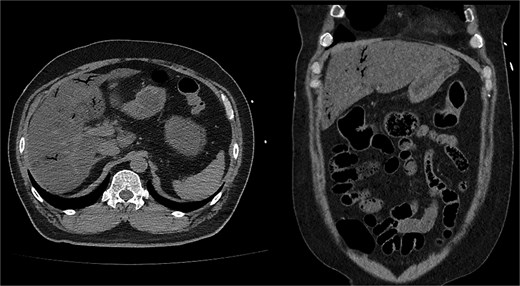

On the first day of ICU admission, the patient received 2000 ml crystalloid fluid and 1300 ml bicarbonate mix fluid. Total fluid input was 5583 ml, and output was 720 ml. Blood glucose was managed by continuous insulin infusion with intermittent bolus administration. The patient was treated with ceftriaxone and metronidazole for suspected bowel ischaemia. ABGA revealed the following: pH 7.36, PCO₂ 18.7 mmHg, PO₂ 85.9 mmHg, HCO₃− 10.4 mmol/l, lactate 6.9 mmol/l, and glucose 423 mg/dl. As hourly urine output remained below 0.5 ml/kg, continuous renal replacement therapy (CRRT) was initiated to resolve volume overload. Dynamic liver CT confirmed diffuse fatty liver, significant thickening, and decreased enhancement of walls in the distal SB and ascending colon, supporting SBI diagnosis (Fig. 2).

Follow-up dynamic liver CT revealed decreased wall enhancement, mural air densities in the distal small bowel and ascending colon compared to the previous noncontrast abdominopelvic CT.